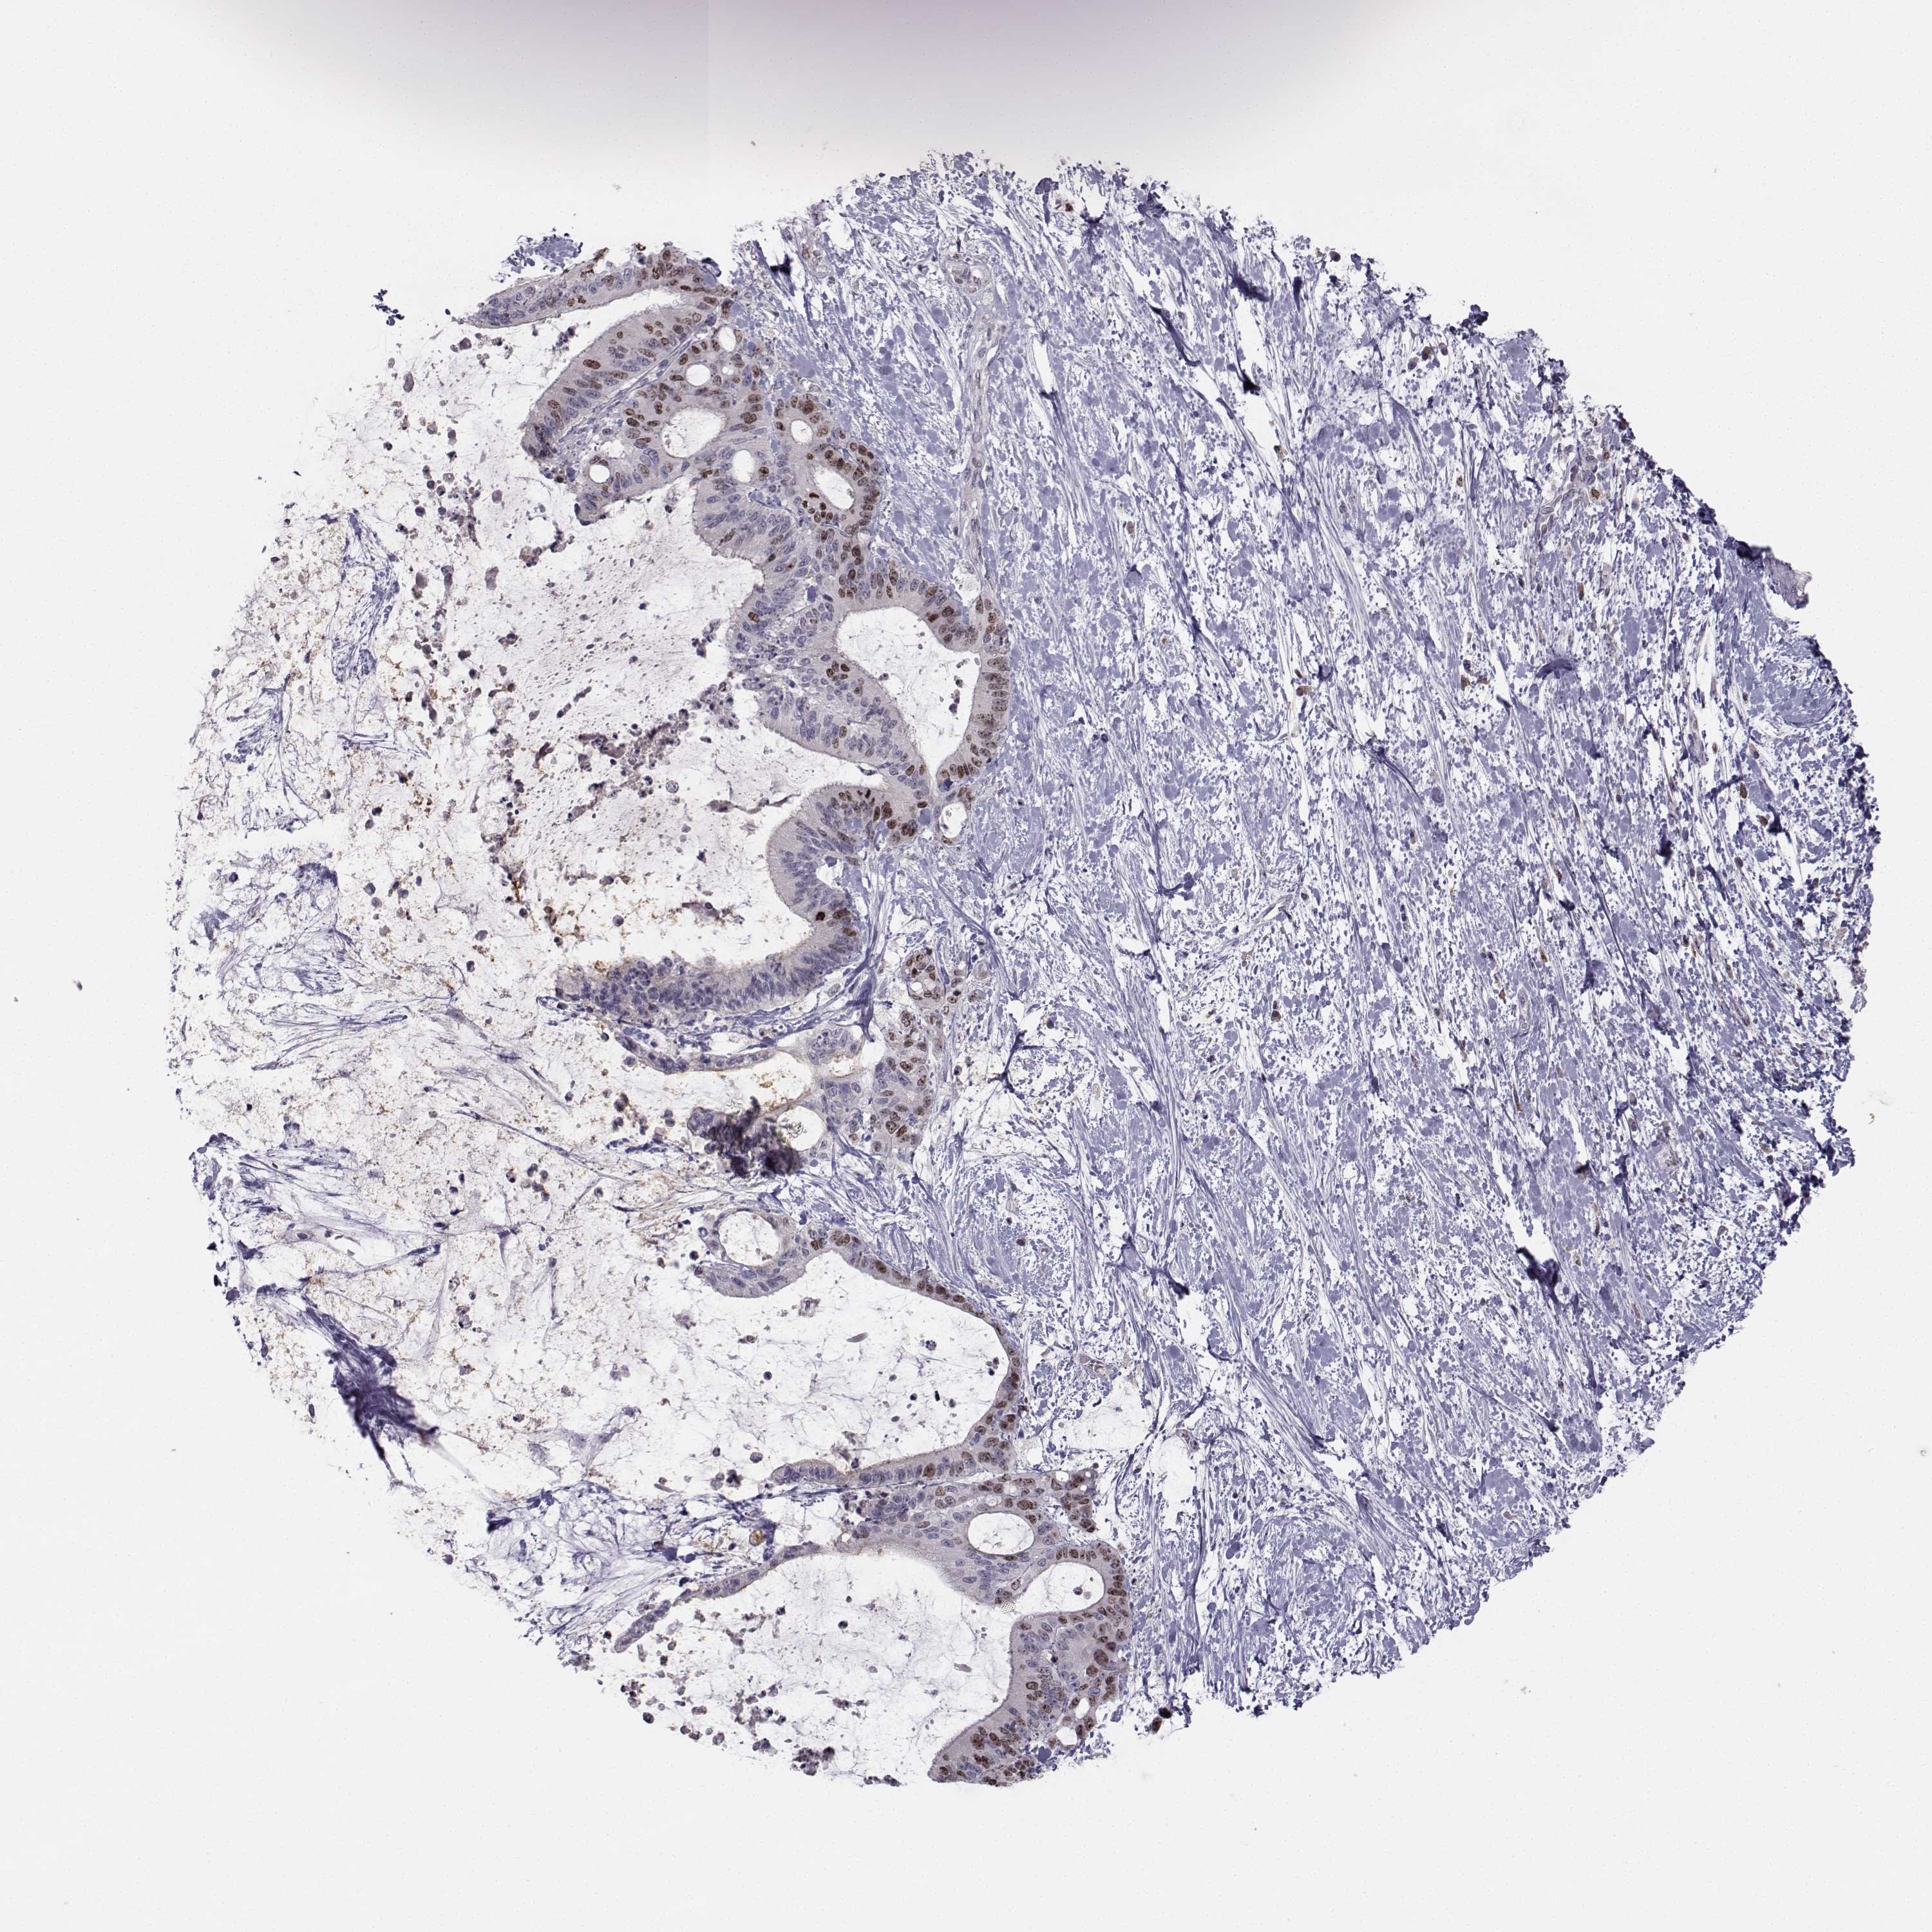

LIVER CANCER - Protein expressioni

A mouse-over function shows sample information and annotation data. Click on an image to view it in a full screen mode. Samples can be filtered based on level of antibody staining by selecting one or several of the following categories: high, medium, low and not detected. The assay and annotation is described here.

Note that samples used for immunohistochemistry by the Human Protein Atlas do not correspond to samples in the TCGA dataset.

Antibody stainingi

Antibody staining in the annotated cell types in the current human tissue is reported as not detected, low, medium, or high, based on conventional immunohistochemistry profiling in selected tissues. This score is based on the combination of the staining intensity and fraction of stained cells.

Each image is clickable and will lead to virtual microscopy that enables deeper exploration of all samples and also displays staining intensity scores, fraction scores and subcellular localization as well as patient and tissue information for each sample.

Antibody HPA073031

Staining

High

Medium

Low

Not detected

Intensity

Strong

Moderate

Weak

Negative

Quantity

>75%

75%-25%

<25%

None

Location

Nuclear

Cytoplasmic/membranous

Cytoplasmic/membranous,nuclear

Carcinoma, Hepatocellular, NOS

Cholangiocarcinoma